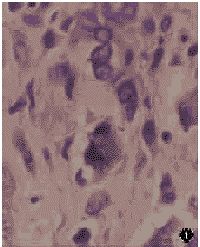

2.光鏡所見腫瘤細胞梭形、多角形、圓形,細胞間變明顯,細胞大小不一,形態各異,細胞核大,核仁明顯,常見病理核分裂,在分化較好的地方可以見到腫瘤細胞的直接形成腫瘤性骨及骨樣組織,呈粉染均質條索狀及小片狀,腫瘤越成熟形成的骨及骨樣組織越多,有時還可見到破骨細胞型巨細胞及出血和壞死區。

(1)骨母細胞型:主要由具有明顯異型性的惡性骨母細胞組成,形成較多的腫瘤性骨及骨樣組織,細胞的分化程度不一,有的分化比較成熟,異型性不明顯,形成瘤骨較多,有的則分化較差,瘤細胞異型性十分明顯,核分裂易見,形成腫瘤性骨及骨樣組織少。

本病的發病機制還不很清楚。它的組織學特點是增生的梭形腫瘤細胞直接產生骨樣基質或不成熟骨。但其髮型不同,組織學特點也不同。本文已在概述中描述。